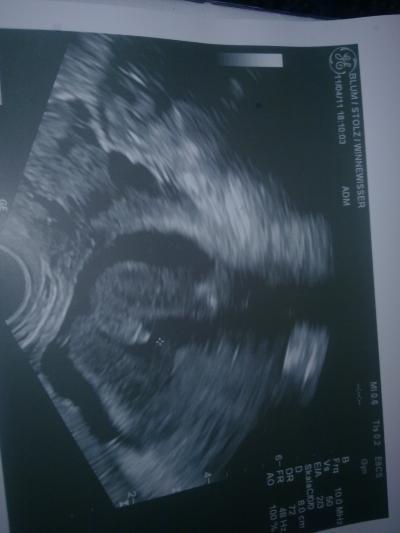

Huhu ihr Lieben, diesmal hatte ich richtig Glück und es gab ein eindeutiges Outing!! :) Ein Junge...anbei auch noch ein ganz ganz tolles Foto! :))) Er ist kerngesund und ca.18cm insgesamt! Ich freue mich sooo....glg

Bild zu Ein 100%iges Outing!! :)) - Forum für September - Mamis